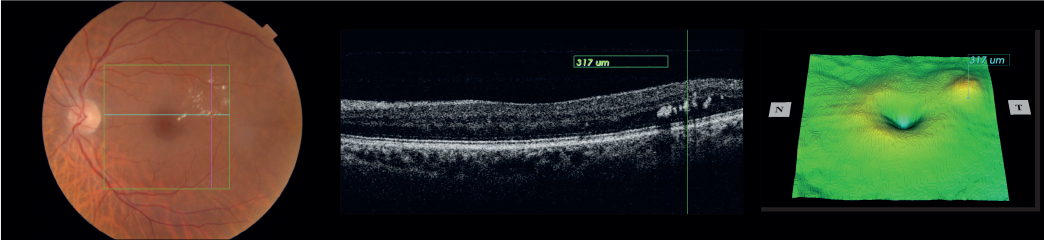

Maestro2, the robotic OCT fundus camera, now with OCTA, offers unparalleled detail in assessing both retinal structure and vascular function—all from a single scan. The Maestro2 provides OCT reference data for the optic nerve, RNFL, ganglion cell, and macular thickness. Plus, you’ll get a true-color fundus photo with pinpoint registration to the OCT.